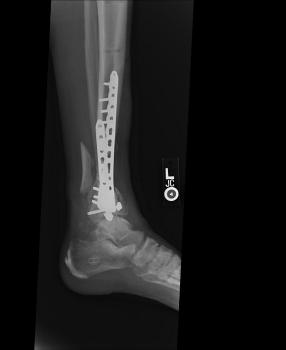

Post-corrective surgery X-Rays of the damaged right & left legs / ankles

The first two x-rays show Liam’s left ankle and pelvis prior to the accident. For comparison purposes it is interesting to see the

differences. The next x-rays were taken after the corrective surgery performed by Dr. Armendariz. Noticed that Dr. Armendariz has used tibia

bracing and also aligned the bone fragments of the left leg so that they could heal in the proper orientation. The external fixation has been

removed and Liam’s left foot has been returned to a more natural alignment.